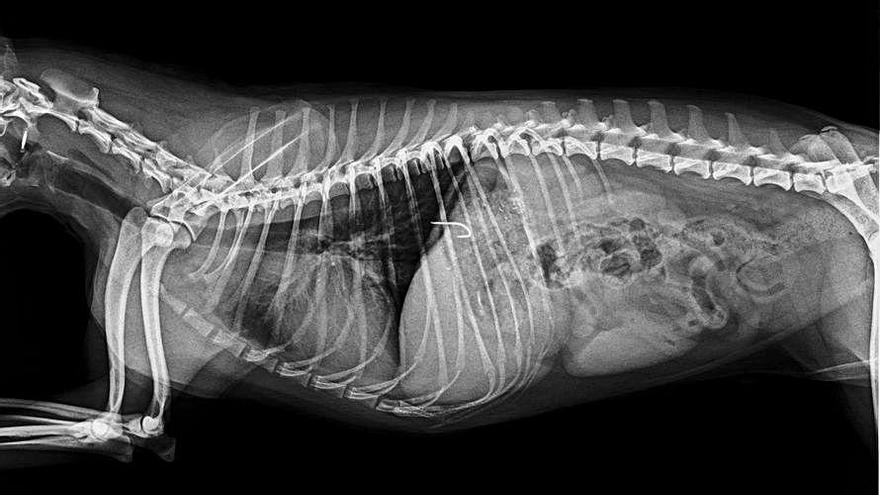

Al menos seis perros que viven en el Molinar se han tragado sin querer anzuelos que se hallaban ocultos entre el cebo desechado por pescadores aficionados. Los ganchos de metal estaban dentro de la pasta de comida para atraer a los peces, que había sido dejada en el suelo o las rocas de la zona de pesca, por lo que el abandono en tierra firme atrajo a los canes. Al ingerir este alimento, que suele estar compuesto por migas de pan, gusanos y restos de comida, seis mascotas como mínimo han tenido que ser operadas con el fin de extraerles los anzuelos y otra más ha sufrido una intoxicación, tal como explica el propietario de uno de los afectados.

Las consecuencias derivadas de estos comportamientos han sido "un sufrimiento traumático" para seis perros, por la intervención quirúrgica y el posoperatorio, sin olvidar el padecimiento del can intoxicado; y "un significativo quebranto económico" para sus dueños, ya que los costes del veterinario superan los 400 euros cuando las mascotas son de mediana estatura y pueden llegar a los 1.000 si son perros de gran tamaño.

El posoperatorio es "delicado y doloroso", y en el caso del can del dueño denunciante, se prolongó unos 20 días, por lo que el sufrimiento también se debe extrapolar a los propietarios, aunque sea de forma indirecta, según dice sobre todos los perjuicios de dejar anzuelos y cebos abandonados.